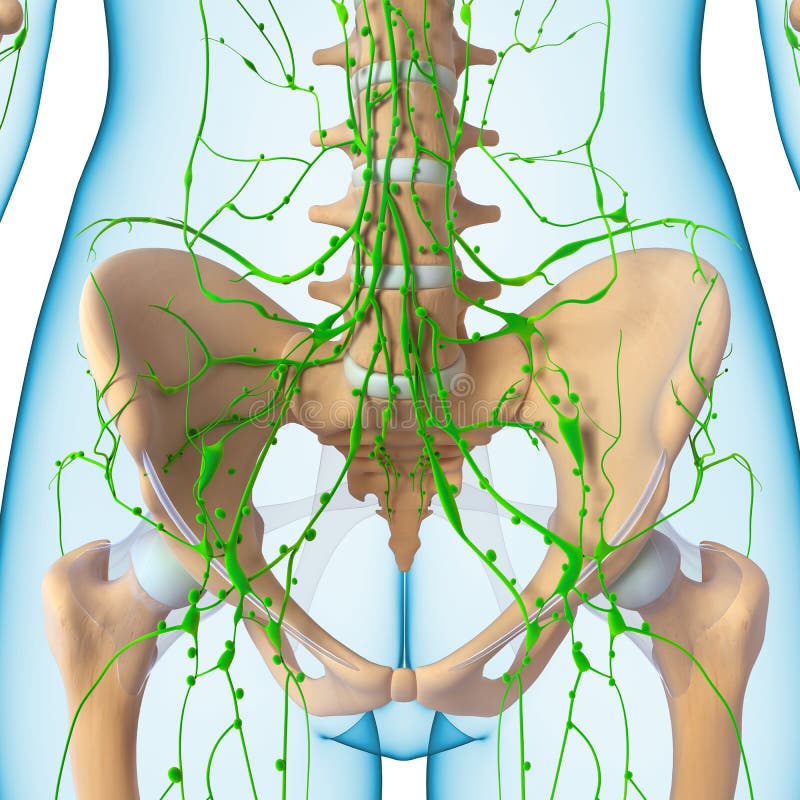

Изображения и схемы: как выглядит лимфа